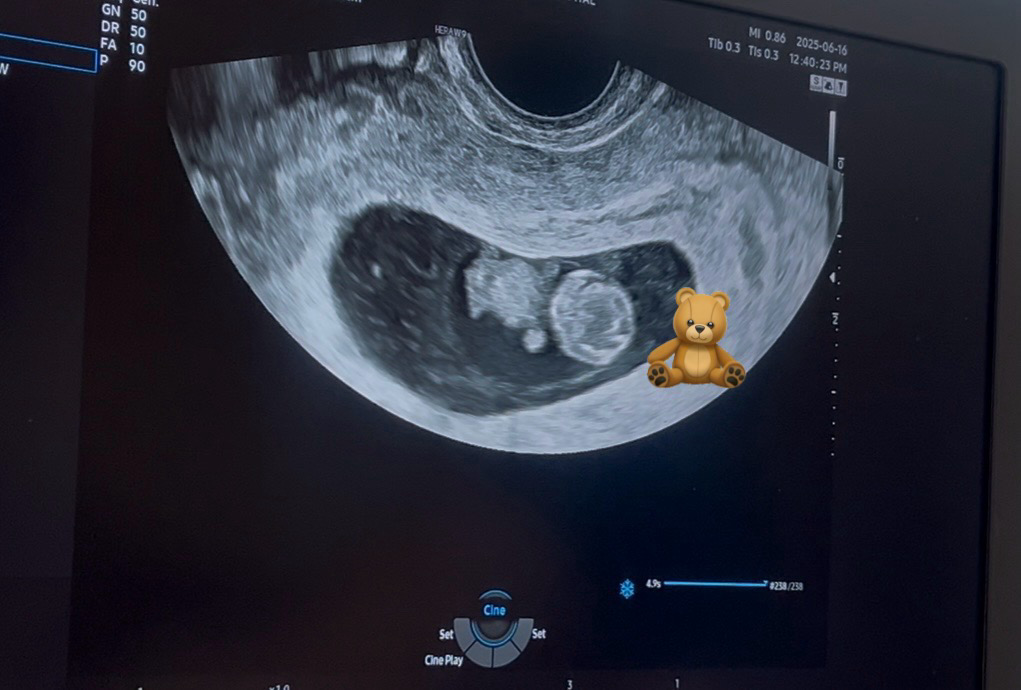

9주 1일차에 보고온 초음파! 젤리곰 맞을까요?

9주 1일차 병원 방문해서 질초음파로 아기 보고 왔는데요🥹 뭔가 눈사람 같기도 하고 ㅎㅎㅎ 지난주에 알아보기 힘들었던 팔다리가 동글동글하게 자라서 잘 보이는데, 이게 바로 8-9주차에 많이 보시는 젤리곰 맞을까요?! ㅋㅋ 꼼지락 꼼지락 움직이는 모습 보여줘서 넘 감동이었어요 ㅠㅠ 입덧때문에 죽을 맛이지만 그래두 아기가 잘 자란 모습보니까 맘이 놓이네용..